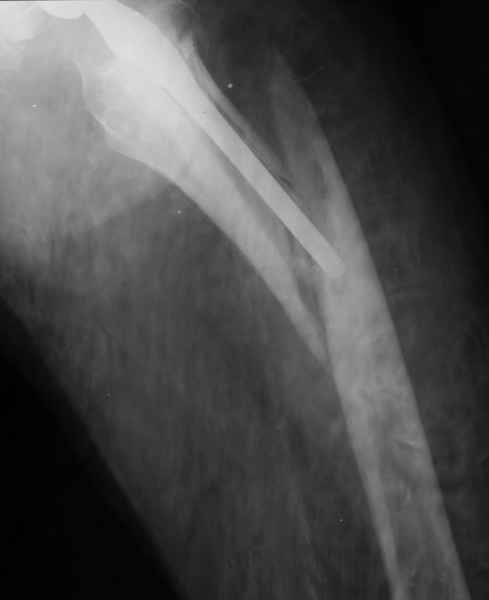

Можно уверенно рассчитывать на сращение фрагментов бедра между собой. Можно ли рассчитывать на реинтеграцию имеющейся ножки в проксимальном отделе - действительно вопрос открытый. Но во всяком случае ножка будет заметное время стабильной за счет дистальной фиксации. Будет ли это время достаточно на всю оставшуюся жизнь пациента - трудно предугадать.

Но, как Александр Виноградский справедливо заметил, после сращения бедра появляется возможность поставить даже обычную ножку большего размера.